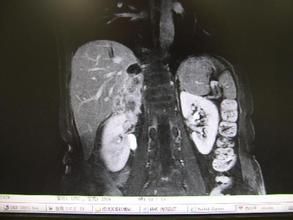

此外,須經B超、CT或MRI檢查腎上腺腫瘤的大小、性質及其與周圍結構的關係,以及顱骨蝶鞍部位的X線正側位攝片、斷層和三維蝶鞍部位的X線正側位攝片、斷層和三維蝶鞍攝片以及CT掃描,磁共振成像診斷垂體腺瘤或微腺瘤的存在與否。

(4)影像學診斷

原醛症除腎上腺腺瘤、腺癌引起者外,腎上腺皮質增生引進者亦占很大比例。前者以手術治療為主,後者須採用藥物治療,兩者方法不同,須通過B超、CT、MRI對三者進行鑑別診斷。由於引起原醛症的腺瘤可能很微小,CT掃描套用間距0.5cm的密層掃描可避免將腫瘤遺漏。鑑別遇到困難時,可套用腎上腺同位素碘化膽固醇閃爍掃描加地塞米松抑制試驗,即給患者注射131I—6β碘甲基—19去甲膽固醇後進行掃描,皮質腺瘤較正常吸收較多量的放射標記物,皮質增生攝取量正常,皮質癌則不顯示。其準確率可達70%~90%。

據文獻統計報告凡有典型發作症狀、腹部腫塊、高血壓、糖尿病、基礎代謝增高等五者之二者,應疑有嗜鉻細胞瘤的存在,五者居三則高度懷疑,居四則可確診無疑。其中以能發現腫塊最為重要,如腫瘤很小,且位於腎上腺外,則必須從定性。定位兩方面著手進行檢查。定性方面,測定尿去甲腎上腺素及腎上腺素、尿3-甲氧基-4-羥基扁桃酸(VMA)值。其正常值為8~165微克/24時。血漿結合狀態的兒茶酚胺測定,在靜息臥位抽血測定血漿兒茶酚胺之值如明顯升高,結合臨床即可確診。如多巴胺值升高,常表面腫瘤為惡性。其準確性優於測血游離狀態的兒茶酚胺值。定位方面:一般採用B超、CT、MRI即可確診腎上腺腫瘤、增生、出血、髓質脂肪瘤等,如缺乏此設備,腹膜後注氣造影仍可採用對腎上腺外的小嗜鉻細胞瘤定位可能仍有困難,可採用下腔靜脈導致管分段抽血檢測血漿兒茶酚胺值或腹主動脈造影尋找線索,如有條件,採用放射性核素碘苄胍(131IMIBG)示蹤掃描行γ照相則更有特效。